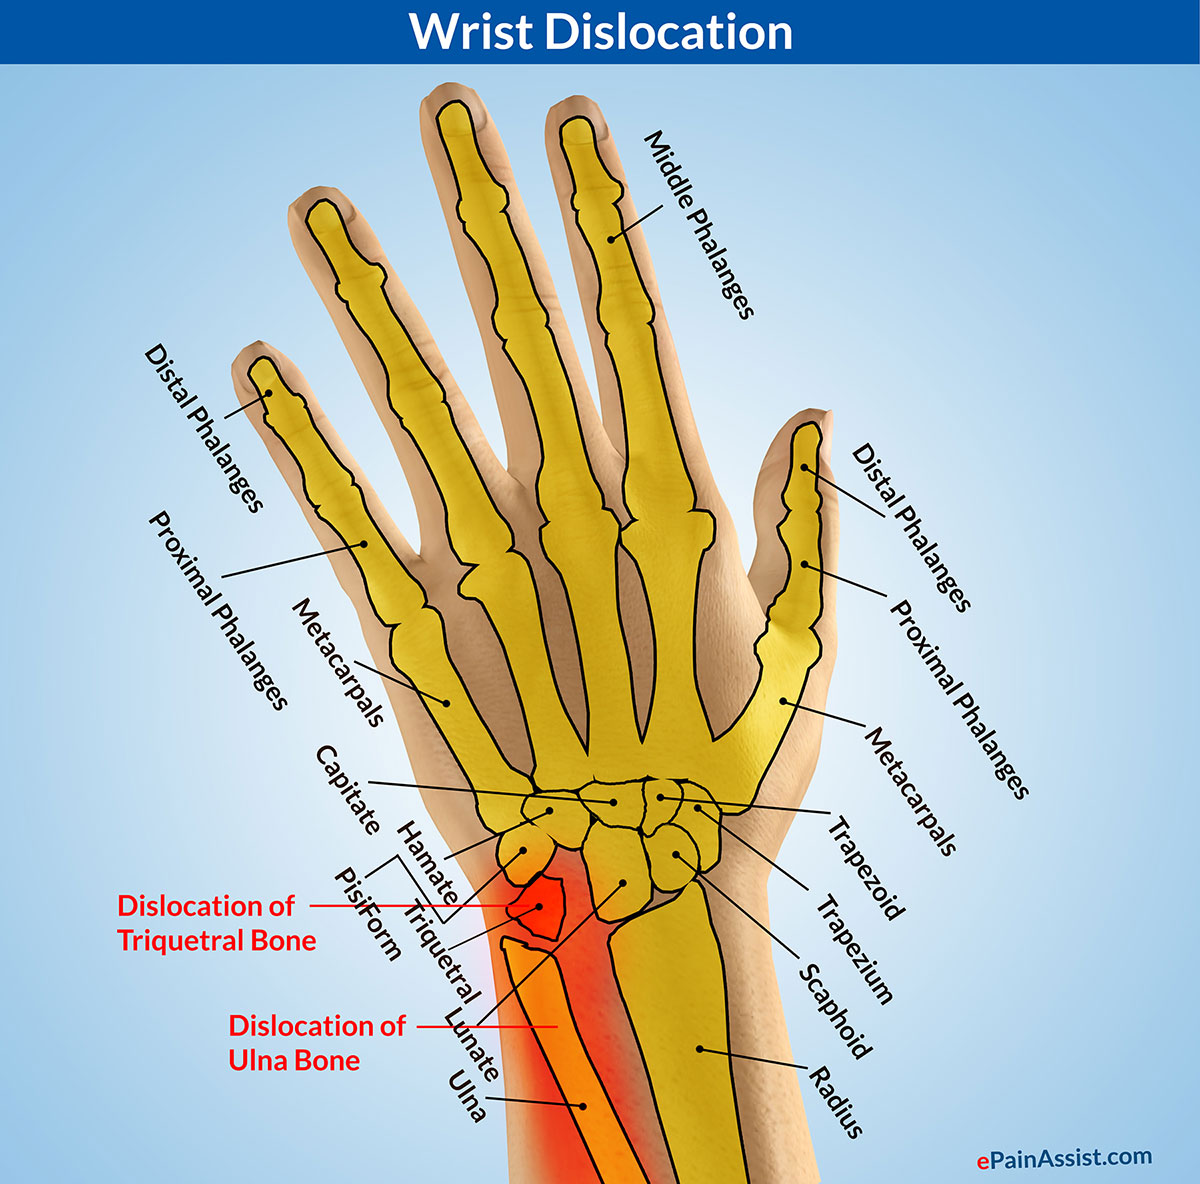

Dislocated wrist | Semantic Scholar

Wrist Dislocation|Types|Causes|Signs|Symptoms|Treatment|Exercises …

Triquetral fracture. (a) PA radiograph of the right wrist demonstrates …